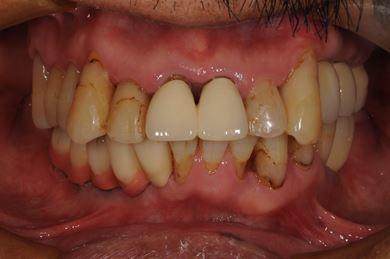

骨再生スピードインプラント治療+遊離歯肉移植

| 主訴 | 入れ歯の部分をインプラントにしたい。 | ||||||||||||||||||||||||||||||||

| 治療内容 | インプラント8本(サイナスリフト、抜歯即日スピードインプラント)、ハイブリッドセラミッククラウン9本、遊離歯肉移植 | ||||||||||||||||||||||||||||||||

| 総治療費 | 2,073,750円 | ||||||||||||||||||||||||||||||||

| 治療期間 | 1年0ヶ月 |